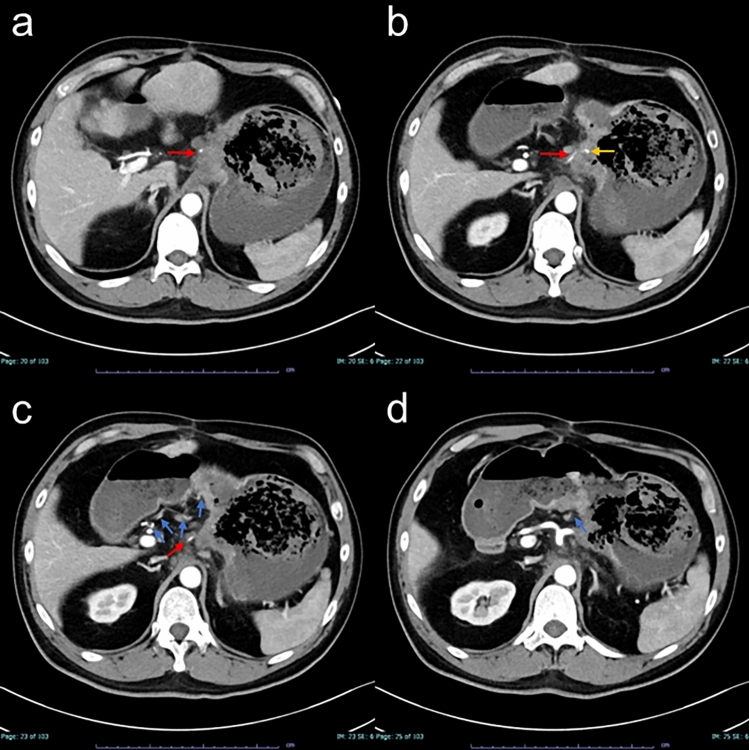

虽然有报道称止血放疗是治疗胃癌出血的有效方法,但其作用机制和即时效果尚不清楚。我们报告了一个胃癌出血的病例,这是由整个胃肿瘤和左侧胃动脉假性动脉瘤在肿瘤相关溃疡处引起的。患者因全胃肿瘤出血行放射治疗,随后经导管动脉栓塞治疗左胃动脉假性动脉瘤。放疗后2小时单段8 Gy x线造影显示,栓塞后的胃左动脉、未栓塞的胃右动脉、胃左动脉和肝左动脉总干的肿瘤血管和肿瘤染色均消失,推测未栓塞动脉的这些血管造影改变反映了止血放疗的即时效果。止血治疗后,患者生命体征稳定,血红蛋白水平未下降,提示立即止血。本病例提示止血机制与早期肿瘤血管改变有关,说明止血放疗可实现快速止血控制。因此,止血放疗应被视为胃癌出血的紧急治疗选择。

Although hemostatic radiotherapy has been reported as an effective treatment for gastric cancer bleeding, its mechanism and immediate effects remain unclear. We experienced a case of gastric cancer bleeding originating from both the whole gastric tumor and a left gastric arterial pseudoaneurysm at the tumor-associated ulcer. The patient was treated with radiotherapy for bleeding from the whole gastric tumor, followed by transcatheter arterial embolization for the left gastric arterial pseudoaneurysm. Angiography performed two hours after radiotherapy with an X-ray of 8 Gy in a single fraction revealed the disappearance of both tumor vessels and tumor stain from not only the embolized left gastric artery but also both the non-embolized right gastric artery and common trunk of the left gastric and the left hepatic arteries, which indicated these angiographic changes of the non-embolized arteries were presumed to reflect an immediate effect of hemostatic radiotherapy. Following hemostatic treatments, the patient's vital signs stabilized, and hemoglobin levels did not decrease, indicating immediate hemostasis. This case suggests a link between hemostatic mechanism and early tumor vessel changes, indicating that hemostatic radiotherapy can achieve rapid bleeding control. Therefore, hemostatic radiotherapy should be considered an emergency treatment option for gastric cancer bleeding.